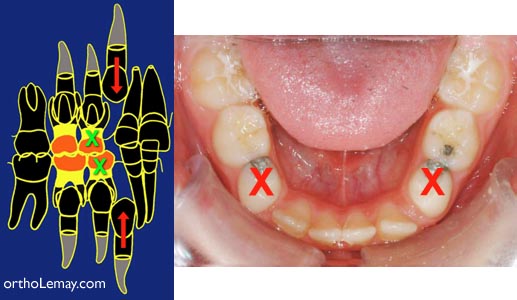

Manque d’espace

En présence d’un manque d’espace sévère pour l’éruption des dents permanentes, des dents temporaires peuvent être extraites (X) pour aider l’éruption des dents permanentes (flèches).